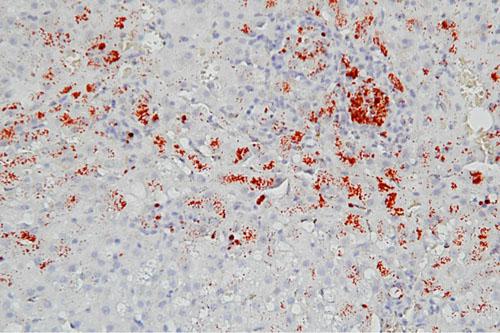

La pathologie hépatique a été diagnostiquée deux ans plus tôt (janvier 2011) lors d’un bilan d’exploration d’une polyuro-polydipsie. L’échographie ayant mis en évidence une hétérogénéité du parenchyme hépatique sans critères diagnostiques spécifiques, une laparotomie avait été réalisée en vue de biopsies. L’examen histologique avait alors montré une hépatite chronique active légérement fibrosante, associée à une surcharge cuprique modérée des zones centro-lobulaires (après coloration à la rhodanine) (photo).

Photo 8 : Lésions histologiques hépatiques